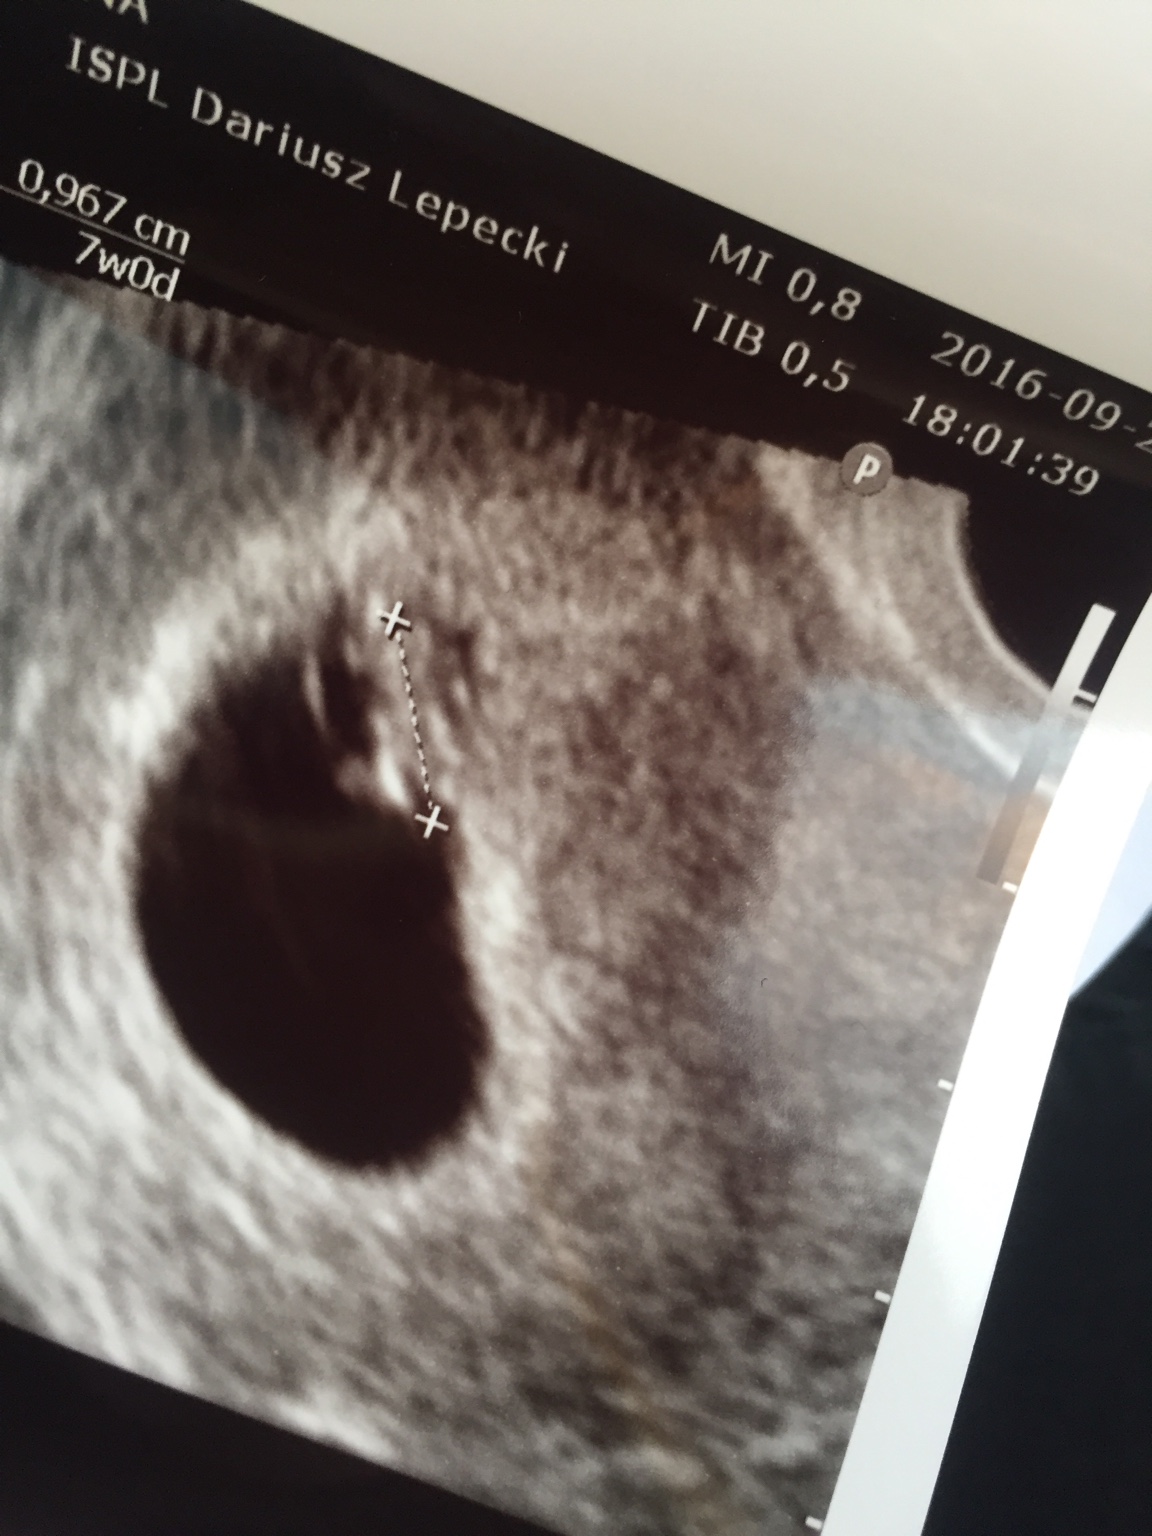

1474995167-rgwar2.jpeg

jest moje 1 cm szczęścia [emoji173]️[emoji7] serduszko cudownie bilo[emoji173]️[emoji173]️[emoji173]️[emoji173]️